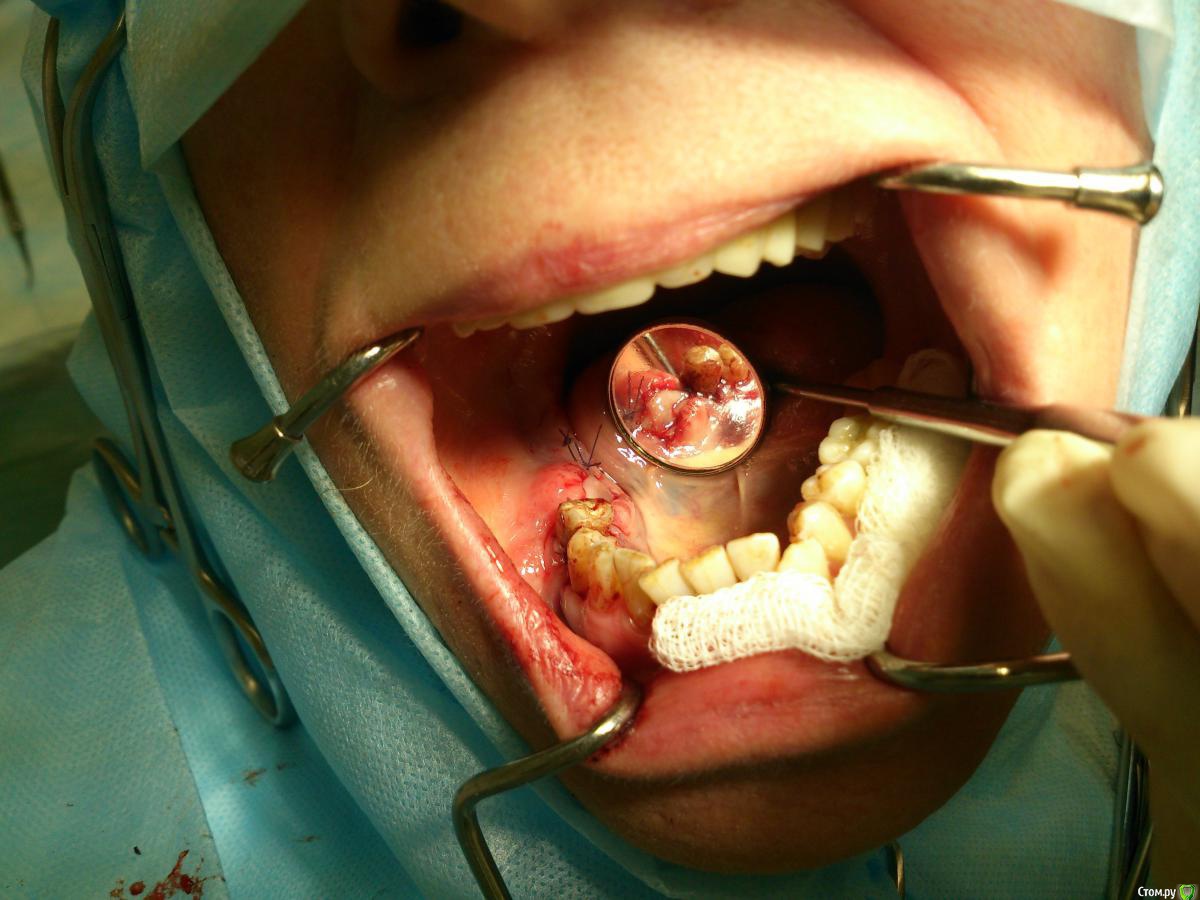

andrey_1965 Опубликовано 21 декабря, 2015 Поделиться Опубликовано 21 декабря, 2015 Ну как результат ?1.-диэпителизация подворот лоскута очень удобно,но опасно для резбы через неделю.язычно-механическая травма через 10 дней через 3недели. На временных доформирую рельеф.2. вроде ничего нештатного через 2недели A-PRF через 5недель убрал все,закрыл мембраной A-PRF две поперек,одна в доль через неделю через 13дней через 21день. Следующий осмотр будет на сроке 5 недель(думаю все сравняется) 3. через неделю 2недели 3недели,на дистальных отмываю помойку4 недели Ссылка на комментарий